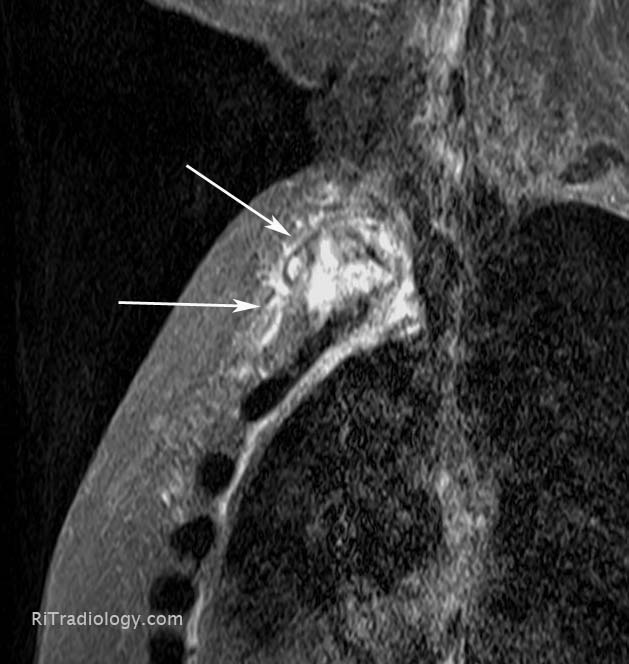

From radiologyinthai.blogspot.co.uk

RiT radiology March 2013 Arthritis Sternum Symptoms Web 6 min read. It causes pain on your left side under your ribs. Costochondritis is inflammation of the cartilage connecting the ribs and. Web what are the symptoms? Web costochondritis is inflammation in the cartilage where your ribs join your sternum. People with costochondritis often experience chest pain in the upper and middle rib area on. Web costochondritis is. Arthritis Sternum Symptoms.